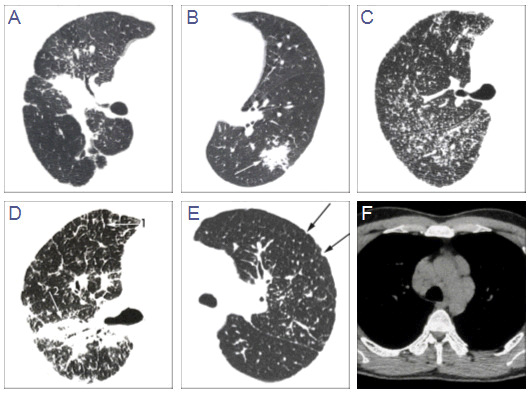

Figure 3 HRCT findings in sarcoidosis adapted from Oberstein et al.[5], visual score. A Thickening or irregularity of the bronchovascular bundle (BVB). B Parenchymal consolidation (including ground-glass opacifications). C Intra-parenchymal nodules. D Septal and nonseptal lines (1→); BVB (2→). E Focal pleural thickening (arrows). F Enlargement of the lymph nodes.

This is the first case highlighting that adalimumab improves respiratory functional impairment, pulmonary damage including HRCT abnormalities (figure 3 A-F), inflammatory characteristics, as well as extrapulmonary involvement, QOL and reduces fatigue in a patient suffering from refractory pulmonary sarcoidosis. Adalumiumab might be considered as a good alternative for infliximab in sarcoidosis.